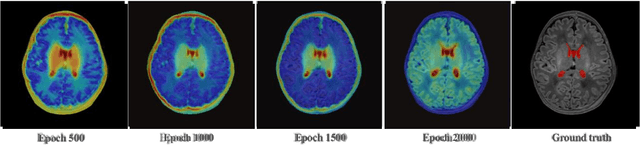

Abstract:Medical image segmentation based on deep learning often fails when deployed on images from a different domain. The domain adaptation methods aim to solve domain-shift challenges, but still face some problems. The transfer learning methods require annotation on the target domain, and the generative unsupervised domain adaptation (UDA) models ignore domain-specific representations, whose generated quality highly restricts segmentation performance. In this study, we propose a novel Structure-Modal Constrained (SMC) UDA framework based on a discriminative paradigm and introduce edge structure as a bridge between domains. The proposed multi-modal learning backbone distills structure information from image texture to distinguish domain-invariant edge structure. With the structure-constrained self-learning and progressive ROI, our methods segment the kidney by locating the 3D spatial structure of the edge. We evaluated SMC-UDA on public renal segmentation datasets, adapting from the labeled source domain (CT) to the unlabeled target domain (CT/MRI). The experiments show that our proposed SMC-UDA has a strong generalization and outperforms generative UDA methods.